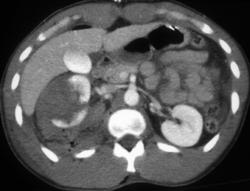

CASE NUMBER 20

Renal Laceration